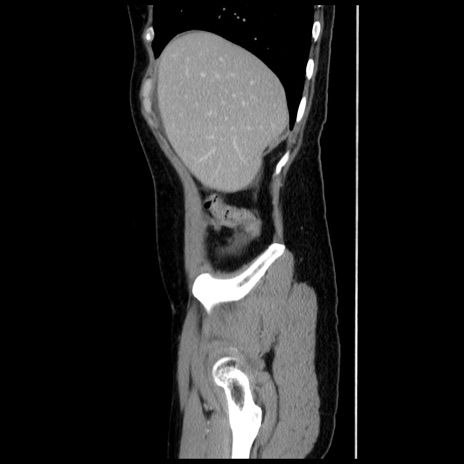

冠状断像

【症例】 50歳代女性

【主訴】 腹痛

【現病歴】前日生レバーを食べた。今朝に排便あり。 昼前に突然発症の腹痛を生じ、当院救急外来を受診した。

【既往歴】 子宮筋腫にてで子宮全摘後

【身体所見】 意識清明、腹部:平坦、軟、下腹部やや左を中心に圧痛・反跳痛あり、筋性防御あり

【データ】WBC 7800、CRP 0.07